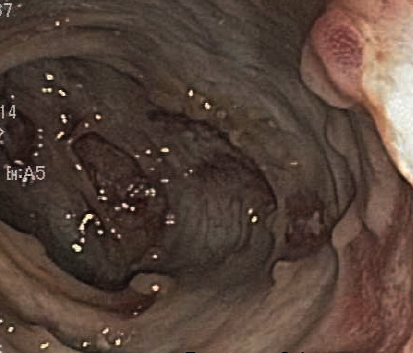

Liza Karamessinis, MD; Catherine Wiley, MD

A 3-month-old boy presented to the pediatrician’s office following 2 episodes of brown emesis.